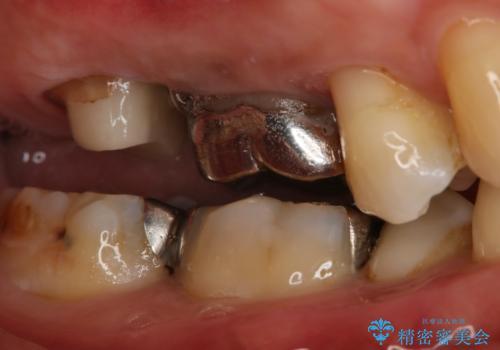

- 右上大臼歯の被せ物が取れたので作り直しを希望された患者様です。

被せ物は白くしたいとのことだったのでフルジルコニアクラウンでの治療を選択しました。

根管治療も必要だったので金属の土台を除去し、新しく土台を立て直した上で被せ物を装着しています。